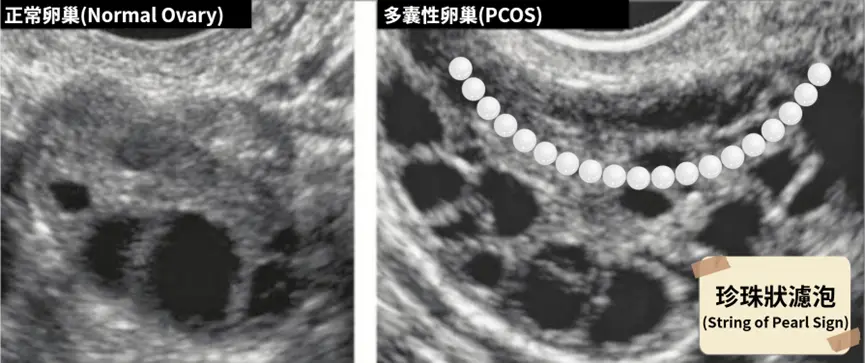

先說結論,超音波只是「輔助」。因為多囊性卵巢的重點其實是「內分泌代謝問題」,而不是超音波的影像本身。我們都知道有部分多囊女性的超音波會看到「珍珠狀濾泡(String of Pearls)」的檢查結果(如圖)。

注意我說的重點,只有「部分」多囊女性會看到這個異常。因為卵巢的型態會因為你的多囊嚴重程度、月經週期、調經藥使用與否、甚至是操作者的切面選擇有關,而且很重要我必須說三次:「超音波不代表你的長期狀態」、「超音波不代表你的長期狀態」、「超音波不代表你的長期狀態」。

且超音波異常真正的意涵是,我們在某一個時間切點,看到了你有一群長不大的濾泡。